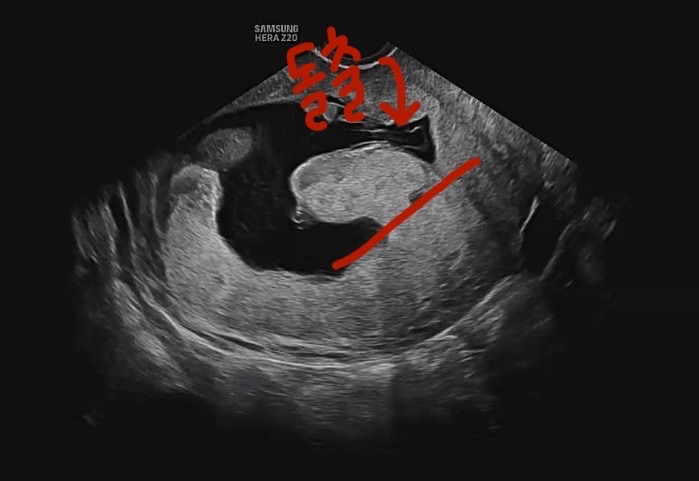

태반 모양

15주 2일차 입미다 약간의 출혈이 있어서 산부인과 갔는데 아기는 잘 있는데 태반이 튀어나왔다고해서 대학병원에 가보라는 소리 듣고 의뢰서까지 받아왔어요 🥲 .. 잘못하면 아이가 크지 못해서 유산 확률도 있댄요 혹시 태반 모양 이상 판정 받으셨던분들 계신가요 🥲